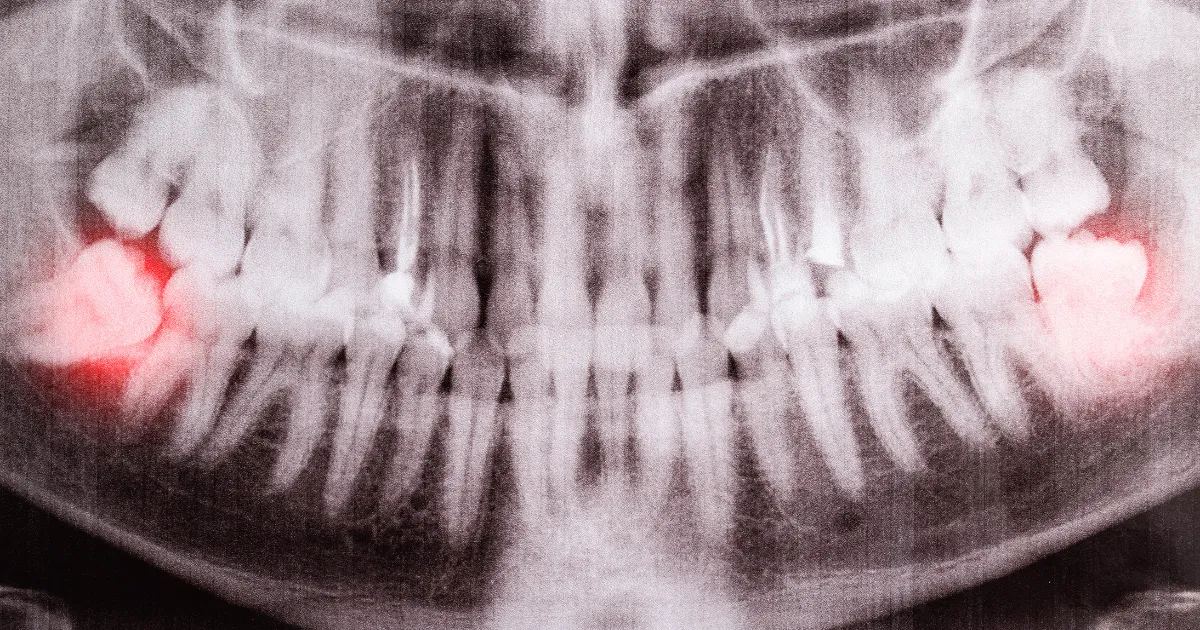

親知らずの抜歯は、埋まっている位置や神経との関係によっては難易度が高くなることがあります。

特に埋伏歯が多い場合や難抜歯が予想される場合には有効です。

事前にレントゲンやCTスキャンを使い、親知らずの位置や神経との関係を詳細に診断します。

複雑な抜歯: 親知らずが歯肉や骨に深く埋まっている場合や、歯の位置が複雑な場合。

CTによる立体画像解析により、神経や血管の位置も明確にし、難易度の高い親知らずの抜歯にも対応しています。